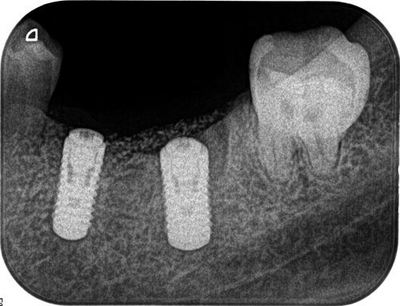

オペ終了時のレントゲン写真です。

約1週間後に抜糸します。

インプラントの埋入トルクが15Ncmを越えていますので

6週間後から咬合できるように準備をします。